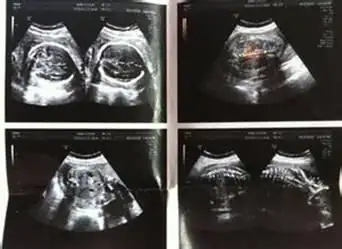

孕晚期,若b超单上经常出现这"5个字"家里可能要添""

妇科b超,请选择最佳检查时间